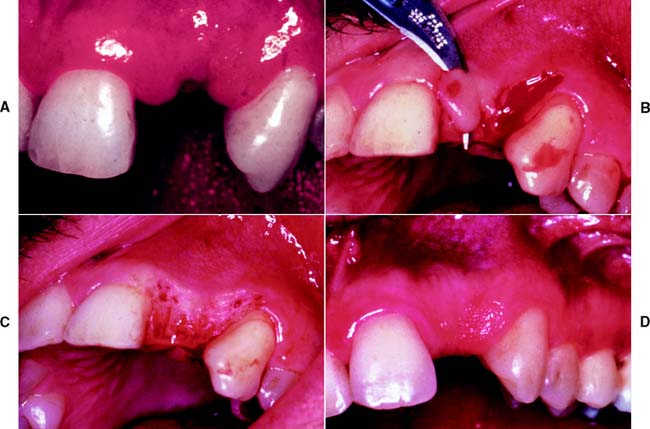

A free (detached) autogenous gingival graft (Fig. 6-13) is used to increase the width of attached gingiva in areas where it is deemed inadequate. The donor site most commonly used is the hard palate, although any area of keratinized tissues, such as an edentulous ridge or the retromolar pad, may be suitable.

Fig. 6-13 Free autogenous gingival graft. A, Planned abutment tooth lacking adequate keratinized gingiva. B, The recipient site is prepared. C, The graft is sutured to place. Some apical adjustment is needed around the premolar before application of the surgical dressing. D, The healed graft. (Compare the width of attached keratinized gingiva here with that in part A.) The defective restoration can be treated at this stage.

The recipient bed site is prepared by making a horizontal split-thickness incision just coronal to the mucogingival junction. As the incision passes apical to the junction, it may become either split thickness or full thickness.36,37 The recipient bed is trimmed of tissue tags and thinned. (A template of tinfoil may be used as a guide for the correct size and shape of the graft.) The graft is then carefully removed from the donor site, and any fat or glandular tissue is excised, so that a maximum thickness of 1 mm is left. Sterile saline is used to keep the graft moist until it is placed on the recipient bed for a check of size and shape, and it is then further shaped if necessary. When the proper dimensions have been attained, the graft is sutured into place. Finally, the graft site and the donor site may be covered with a surgical dressing. Complete healing requires approximately 6 weeks,38,39 at which time the donor site and the grafted site should appear normal.